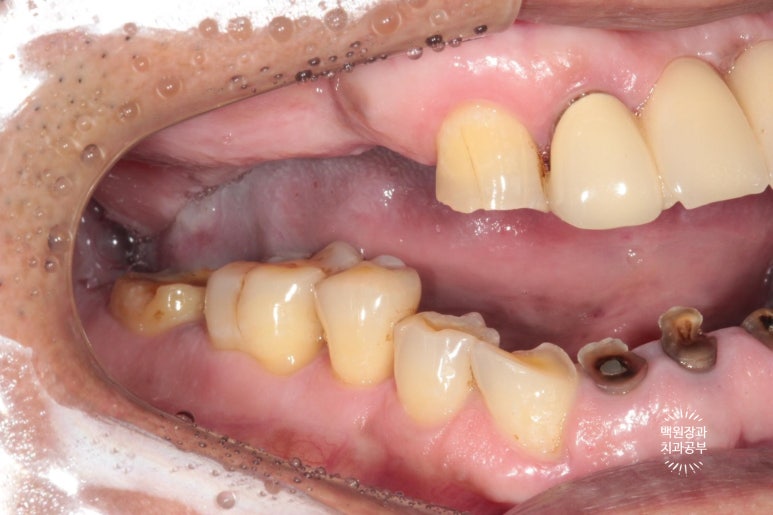

시간이 흘러 잇몸이 아물고 위 임플란트의 임시 보철물을 제작해 드렸습니다.

왼쪽은 임플란트에 맞춤형 지대주 (custom abutment)를 연결한 사진이고,

오른쪽은 그 맞춤형 지대주에 임시치아 (temporary crown)을 접착한 사진입니다.

왜 임시 치아를 만드냐구요?

이렇게 오랜만에 어금니가 생기는 경우, 환자분이 쉽게 적응하여 씹는 기능을 발휘하시기 쉽지 않아요.

저는 재활치료라는 표현을 쓰는데요, 마치 재활치료를 하듯 새로 생긴 임플란트를 사용하는 연습시간을 갖는것이지요. 보통 빠르면 2주, 느리면 4주 정도 걸렸던 것 같아요.

같은 방법으로 아래 앞니에 맞춤형 지대주와 임시치아를 제작하여 접착해드렸어요.

이제 슬슬 치료가 끝나가는게 보이실거에요!

색상이 다소 맞지 않습니다만, 이는 플라스틱 재질과 비슷한 임시치아이므로 기능을 잘 하실 수 있는지 평가하는데 집중해봅니다.!!

양쪽 어금니가 잘 물리고 이제 밥을 먹을 수 있어요.

이렇게 얘기하시면 이제 치료의 끝이 보이는겁니다.ㅠㅠ